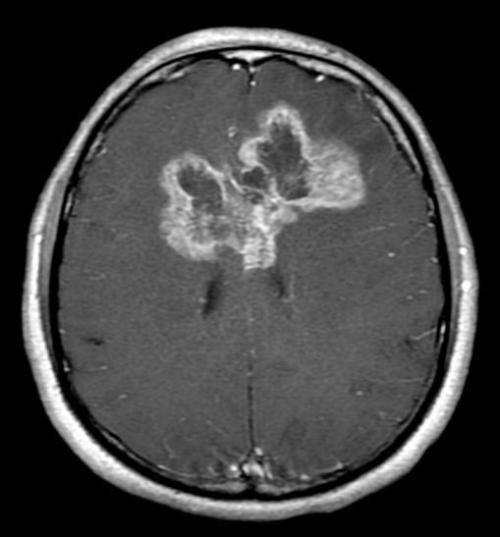

众所周知,胶质母细胞瘤(GBM)是胶质瘤中恶性程度最高的致命脑癌,美国癌症协会估计,55岁以上恶性胶质瘤患者的5年存活率仅有4%。患者即使采用了最为积极的治疗手段,中位生存期仍然少于15个月。(注:麦凯恩已经81岁了)

华人科学家首次利用靶向CD70的CAR-T疗法治疗胶质母细胞瘤